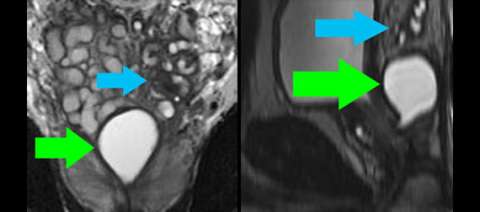

LEFT: Coronal high-resolution T2-weighted image shows a Muellerian duct remnant cyst in the superior prostate (green arrow) and atrophic seminal vesicles on one side only (blue arrow). A utricle cyst, which is much more common, would like lower in the prostate at the level of the verumontanum.

RIGHT: Sagittal reformat of isovolumetric T2-weighted image shows the location of the Muellerian duct remnant cyst (green arrow) with respect to the urethra and bladder.